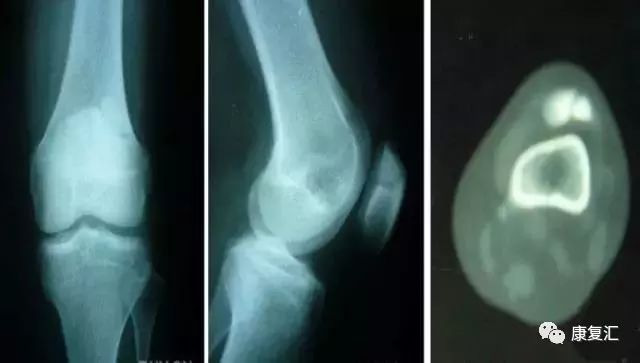

剥脱性骨软骨炎

关节内的骨软骨病,病因不明,关节软骨和软骨下骨变性和再钙化,最常见于股骨内髁,模糊的、定位不清的膝关节疼痛,有晨僵,反复的关节内积液(轻度)。如有游离体,可发生交锁症状。股四头肌萎缩,受累股骨髁关节软骨面压痛。

X线平片显示骨软骨病损或关节内游离体。如怀疑剥脱性骨软骨炎,摄片应包括前后位、后前隧道位、侧位和髌股关节切线位。